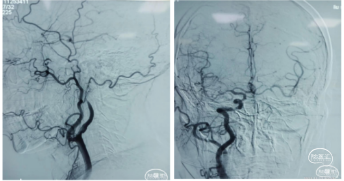

脑血管造影:左侧颈内动脉C 1段呈火苗样,考虑T型段闭塞可能。右侧颈内动脉通过前交通向左侧大脑中动脉区域代偿供血。后交通向左侧大脑中动脉区域供血。可能考虑FLER已经出现病灶,未进行急性血管开通。

错过了最佳治疗血管内介入。

治疗后转康复科,进行康复治疗。康复治疗中停双联抗血小板治疗,又错失了最佳双抗治疗。

患者出现意识不清,病情加重。查CT左侧大脑中动脉区域水肿,低密度改变,中线移位。为大脑中动脉闭塞后改变,恶性脑水肿。